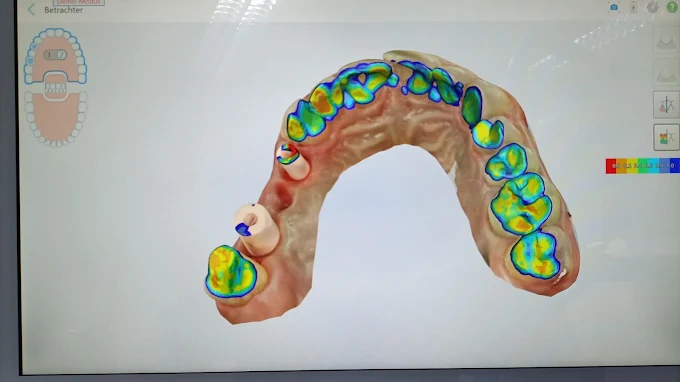

Wir bieten Ihnen ein umfangreiches Spektrum zahnmedizinischer Behandlungen mit modernster Technik und einem erfahrenen Team.

ZahnMedizin heißt für uns, durch sorgfältige Analyse Ihrer Befunde und Berücksichtigung Ihrer persönlichen Ansprüche Lösungen für Ihre individuellen Fragestellungen zu finden.

Moderne Ausstattung und eine wohlfühlende Atmosphäre für Ihre Behandlung